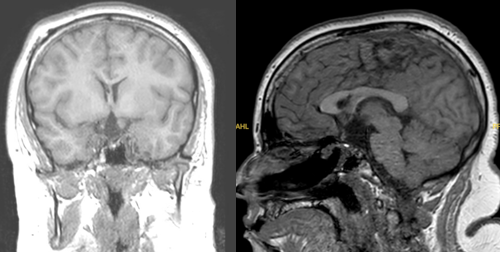

小凯脑肿瘤反复发作的根源,手术后肿瘤残留过多是关键。颅咽管瘤的治疗,要全部和安全的切除肿瘤是重要的,同时必须保留神经、垂体,保障患者正常的发育生长。

第四次手术,究竟还能有多少效果?小凯父母不知道,但是他们依然想要为孩子争取更好的预后。而这一次他们找到了巴教授,肿瘤顺利全切。